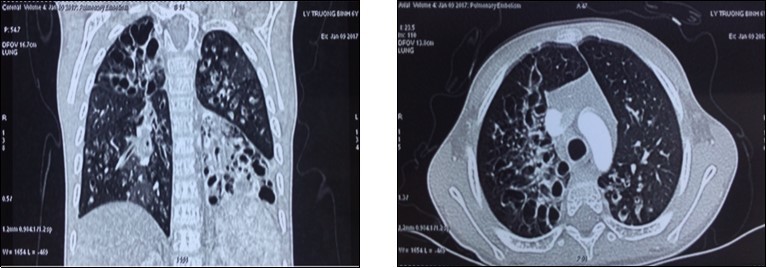

A 7 years old boy was diagnosed of difuse congenital bronchiectasis with chronic respiratory failure and cor pulmonale. At the age of 2 months, he had many respiratory infections. When he was 2 years old, respiratory infection became more frequently, he has been usually hospitalized due to uncontrolled recurent respiratory infection. His main complains were frequent cough with sputum and shortness of breath. On September 2016 patient hospitalized with fever, cough with sputum purulence, severe dyspnea (mMRC of 4 points), cyanosis, difuse crackles in the both lungs, and severe malnutrition (height: 90 cm, weight: 11 kg, BMI: 13.5). The subclinical tests: PaO2: 77 mmHg, PaCO2: 46 mmHg, pH 7.46, SaO2 95% and HCO3-26.7mmol/l. CT-scan: severe difuse bronchiectasis; ECG: sinus tachycardia, right atrial hypertrophy; echocardiography: right ventricle enlargment, pulmonary arterial hypertension (47 mmHg). Blood group: O (+), Rh (D) (+); HLA class I: A02; A24; B13, B52; HLA class II: DRB1 01; DRB1 14. (Image 1)

Image 1.The chest CT-scan image of receipient (difuse bronchiectasis)